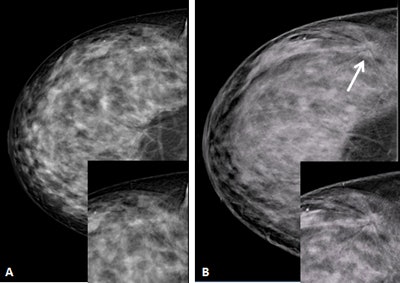

A 48-year-old woman with heterogeneously dense breasts. A: Negative craniocaudal mammogram with electronic magnification of the external area. B: Craniocaudal digital breast tomosynthesis image (Giotto Tomo, IMS, Bologna, Italy) clearly shows a spiculated mass (arrow). Both insets show magnification. Pathology: 12-mm invasive ductal cancer. Image courtesy of Francesco Sardanelli.Frigerio aims to confirm that mammography screening is an effective and efficient health intervention that may reduce breast cancer mortality in excess of 40% in those attending -- at a cost-effectiveness ratio competitive with other medical interventions. More important than denigrating antimammography screening studies, however, is to reinforce the wealth of available data and the scientific strength of the studies that do show significant benefits of mammography screening programs, he told ECR Today.